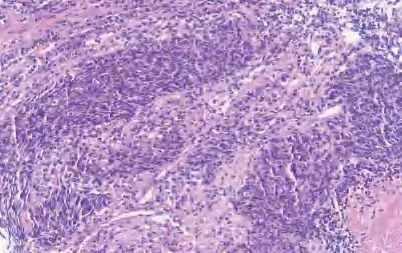

【定义】类癌是恶性LNEN伴分化良好的器官样结构,它包括两类:典型类癌(TC),核分裂<2个/2 mm 2 ,缺乏坏死(图2-13);不典型类癌(AC),核分裂为2~10个/2 mm 2 和(或)坏死,通常为点灶状(图2-14)。

图2-14 AC

【镜下形态】TC和AC为分化好的NET伴有独特的肿瘤结构和细胞学特征。肿瘤细胞为小至中等大小,呈立方形、多角形或梭形(梭形细胞尤其易发生在周围型病变中),形态较一致,核仁不明显,核染色质呈细颗粒状、中至大量嗜酸性颗粒胞质。临床上TC为低级别,AC为中级别,二者的区别在于核分裂象和有无坏死。也可见到嗜酸性颗粒细胞、透明细胞和含色素的类癌。与LCNEC和SCLC不同,伴有SCC或腺癌的复合型类癌不常见。此外,类癌不与SCLC和LCNEC混合存在。罕见的类癌,形态符合不典型类癌,但核分裂象>10个/2 mm 2 或Ki-67增殖指数偏高(>30%),有限的病例基因学分析显示其与类癌关系密切,而不是SCLC和LCNEC(缺乏RB1或TP53基因突变,低的总肿瘤负荷或MEN1基因突变的存在)。类癌肿瘤细胞呈低分子CK阳性,高分子CK阴性;神经内分泌标记CgA、Syn、CD56、INSM1呈强阳性。周围型肿瘤TTF-1呈阳性,中央型肿瘤TTF-1呈阴性。尽管Ki-67增殖指数>5%更可能是AC,但Ki-67的增殖指数不是肺类癌的诊断标准,尤其在TC与AC的鉴别中。Ki-67的主要作用是在挤压的细胞学或小活检中排除SCLC或LCNEC。